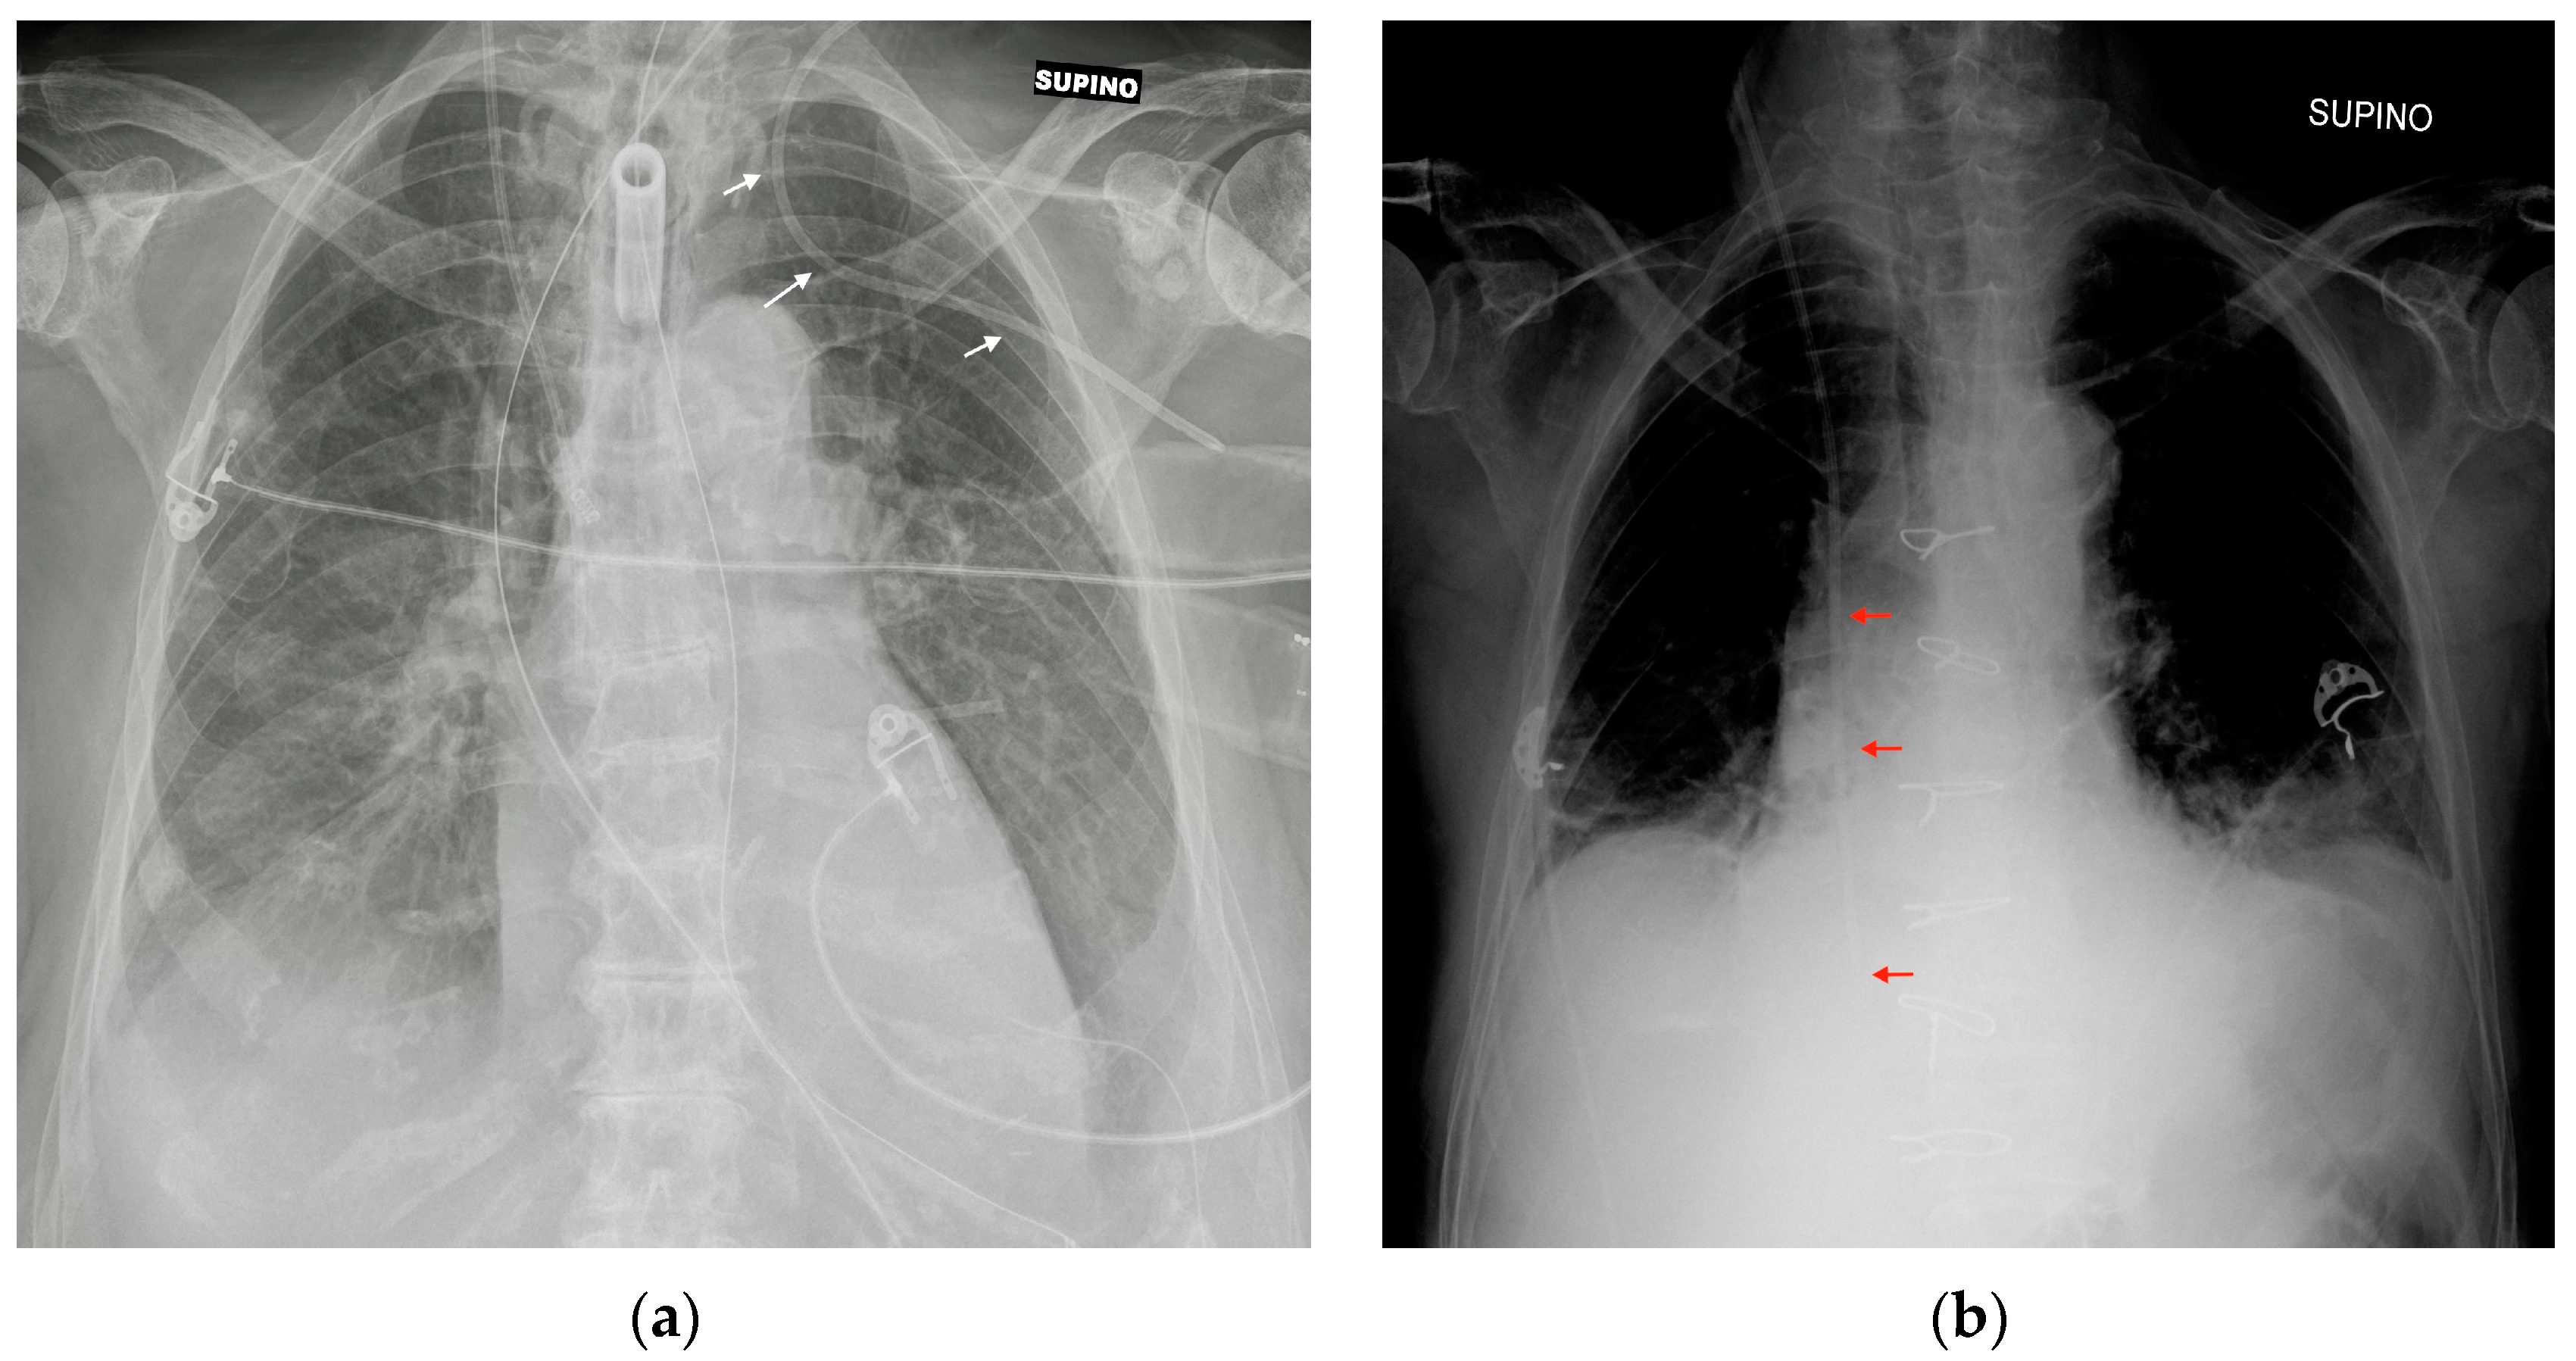

The most common CXR-detectable complications are pneumothorax, malposition (looping, inferior vena cava (IVC) positioning of the tip, wrong thoracic vein positioning), or, less often, vascular perforation, with the catheter located inside the thorax (Figure 3, Figure 4 and Figure 5, Table 2) [6,7].

Figure 3.

Mispositioned CVCs. (a) Left jugular-inserted CVC with its tip inside the left axillar vein (white arrows). (b) Right jugular CVC with its tip inside IVC (red arrows). Note that due to underexposure during acquisition of the CXR, the tip of the catheter is hard to see in the upper abdomen.